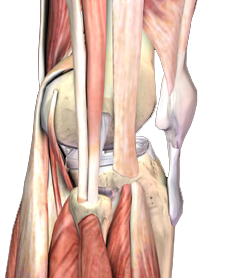

髕骨肌腱